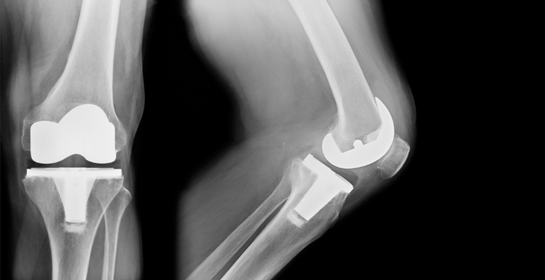

Icon Preoperative Assessment: Includes X-rays, blood tests, and physical evaluation.

Icon Joint Preparation: Damaged cartilage and bone are removed.

Icon Implant Placement: Prosthetic components are fixed in place.

1. Total Knee Replacement (TKR)

Icon Involves replacing the entire knee joint with prosthetic components.

Icon Recommended for severe arthritis affecting the whole joint.

Icon Restores full knee function and reduces chronic pain.